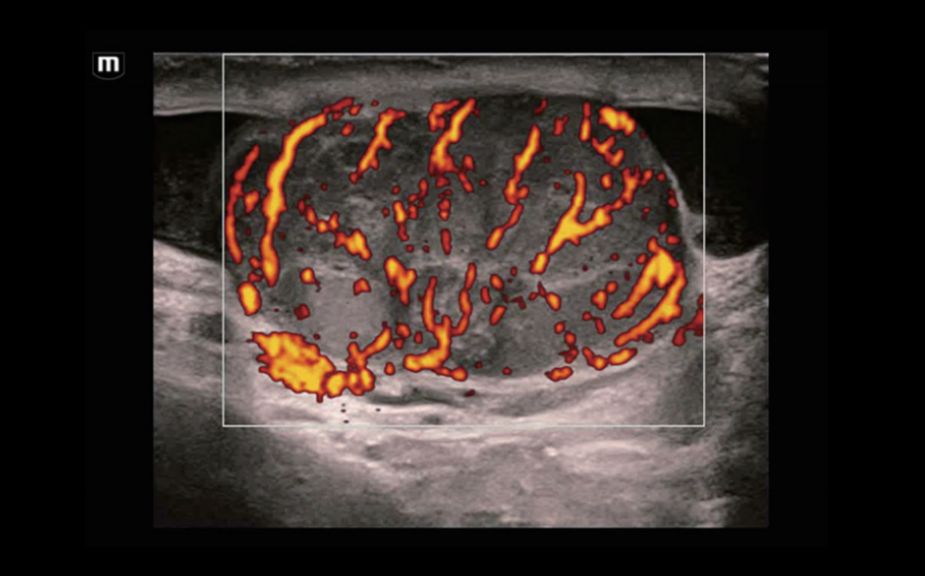

Диагностика очаговых поражений с помощью контрастов: контраст-усиленная визуализация UWN+

Использование как второй гармоники, так и нелинейных фундаментальных сигналов

Высокая чувствительность к низкоамплитудным сигналам и большее время персистенции контрастного вещества

КУУЗИ: метастатический рак печени

КУУЗИ: перфузия аденомы щитовидной железы